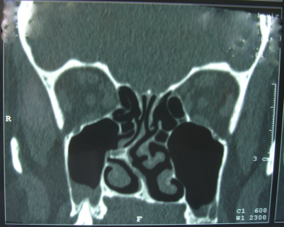

Le chirurgien va modeler la cloison nasale pour rétablir sa rectitude. dans la partie antérieure la cloison nasale est de nature cartilagineuse. dans la partie postéreure, elle est de nature osseuse. on trouve souvent une déformation à ce niveau sur l’os Vomer : on parle d’éperon vomérien qui obstrue tout ou partie de la fosse nasale.

Photo éperon vomerien